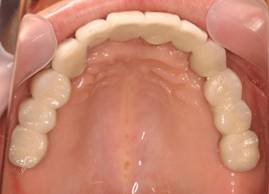

術後。上部構造はハイブリッドレジンです。しっかり嚙めるようになり喜んでいただきました。

上顎

上部構造装着後6年。ハイブリッドレジンを使用したため、少し艶がなくなってきました。上部構造の材料には金属、ハイブリッドレジン、セラミックなどがあります。セラミックはきれいですが欠けやすいため、最近はフルジルコニアを使っています。

上顎 少しすり減ってきました。